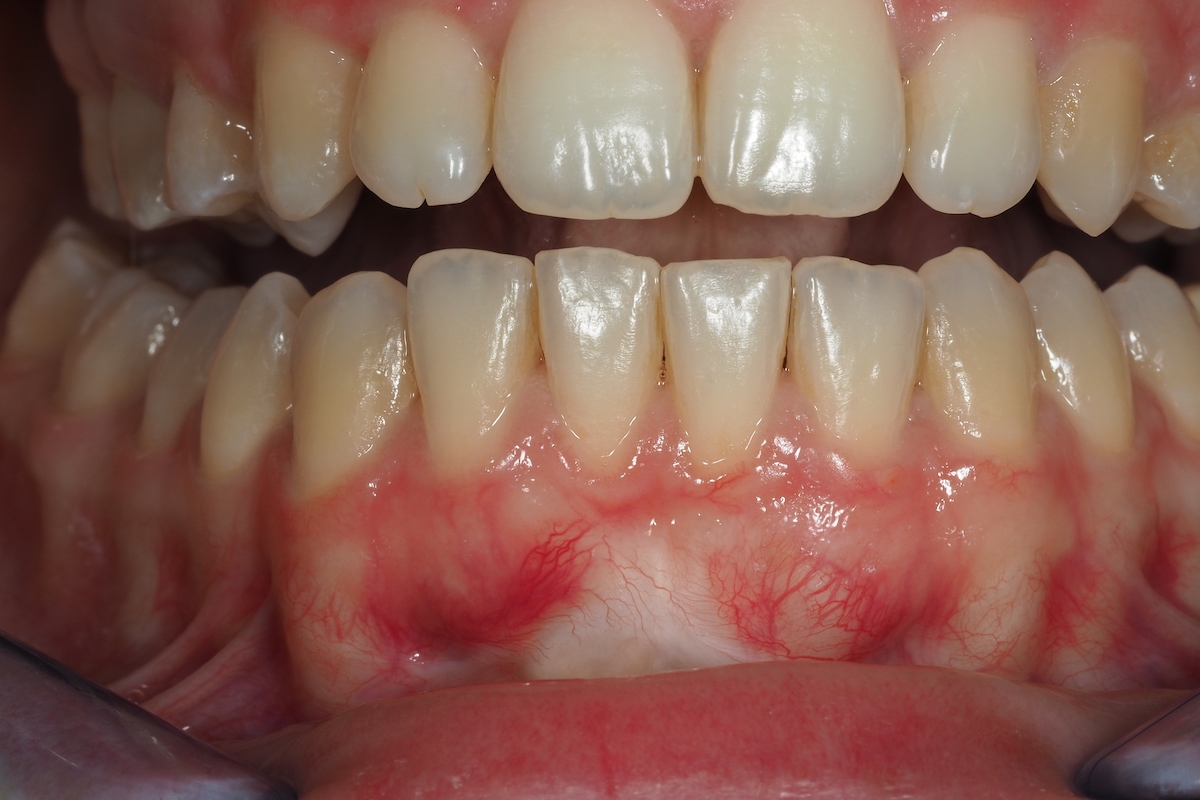

Una de las manifestaciones más frecuentes e iniciales es la gingivitis, un proceso inflamatorio de las encías que se muestran irritadas, inflamadas, enrojecidas y puede producir dolor y sangrado al cepillado con exudado purulento. Además, es habitual presentar halitosis o mal aliento.

Caso de Periodoncia 1 | Tratamiento Gingivitis

Después Después

Antes Antes